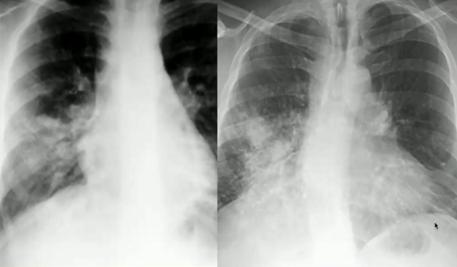

①肺水肿

最初出现弥漫对称的间质性线状阴影,延伸到胸膜边界时表现为横条细线状(KeyleyB征),还可有胸腔积液、上肺血管增粗表现;晚期严重可出现肺实变(从间质累及到肺泡累及),出现蝙蝠翅膀征(严重急性肺水肿时,出现沿肺门翅膀样阴影)。

心源性肺水肿可有明显的心界增大。

图18.线状间质阴影(左);Keyley B征(右)

图19.心源性(左)/非心源性(右)肺水肿

图20.心源性肺水肿:心影增大(绿)、线状间质阴影(蓝)、胸膜增厚(红,卧位时胸腔积液表现)②气胸、纵隔积气、心包积气鉴别